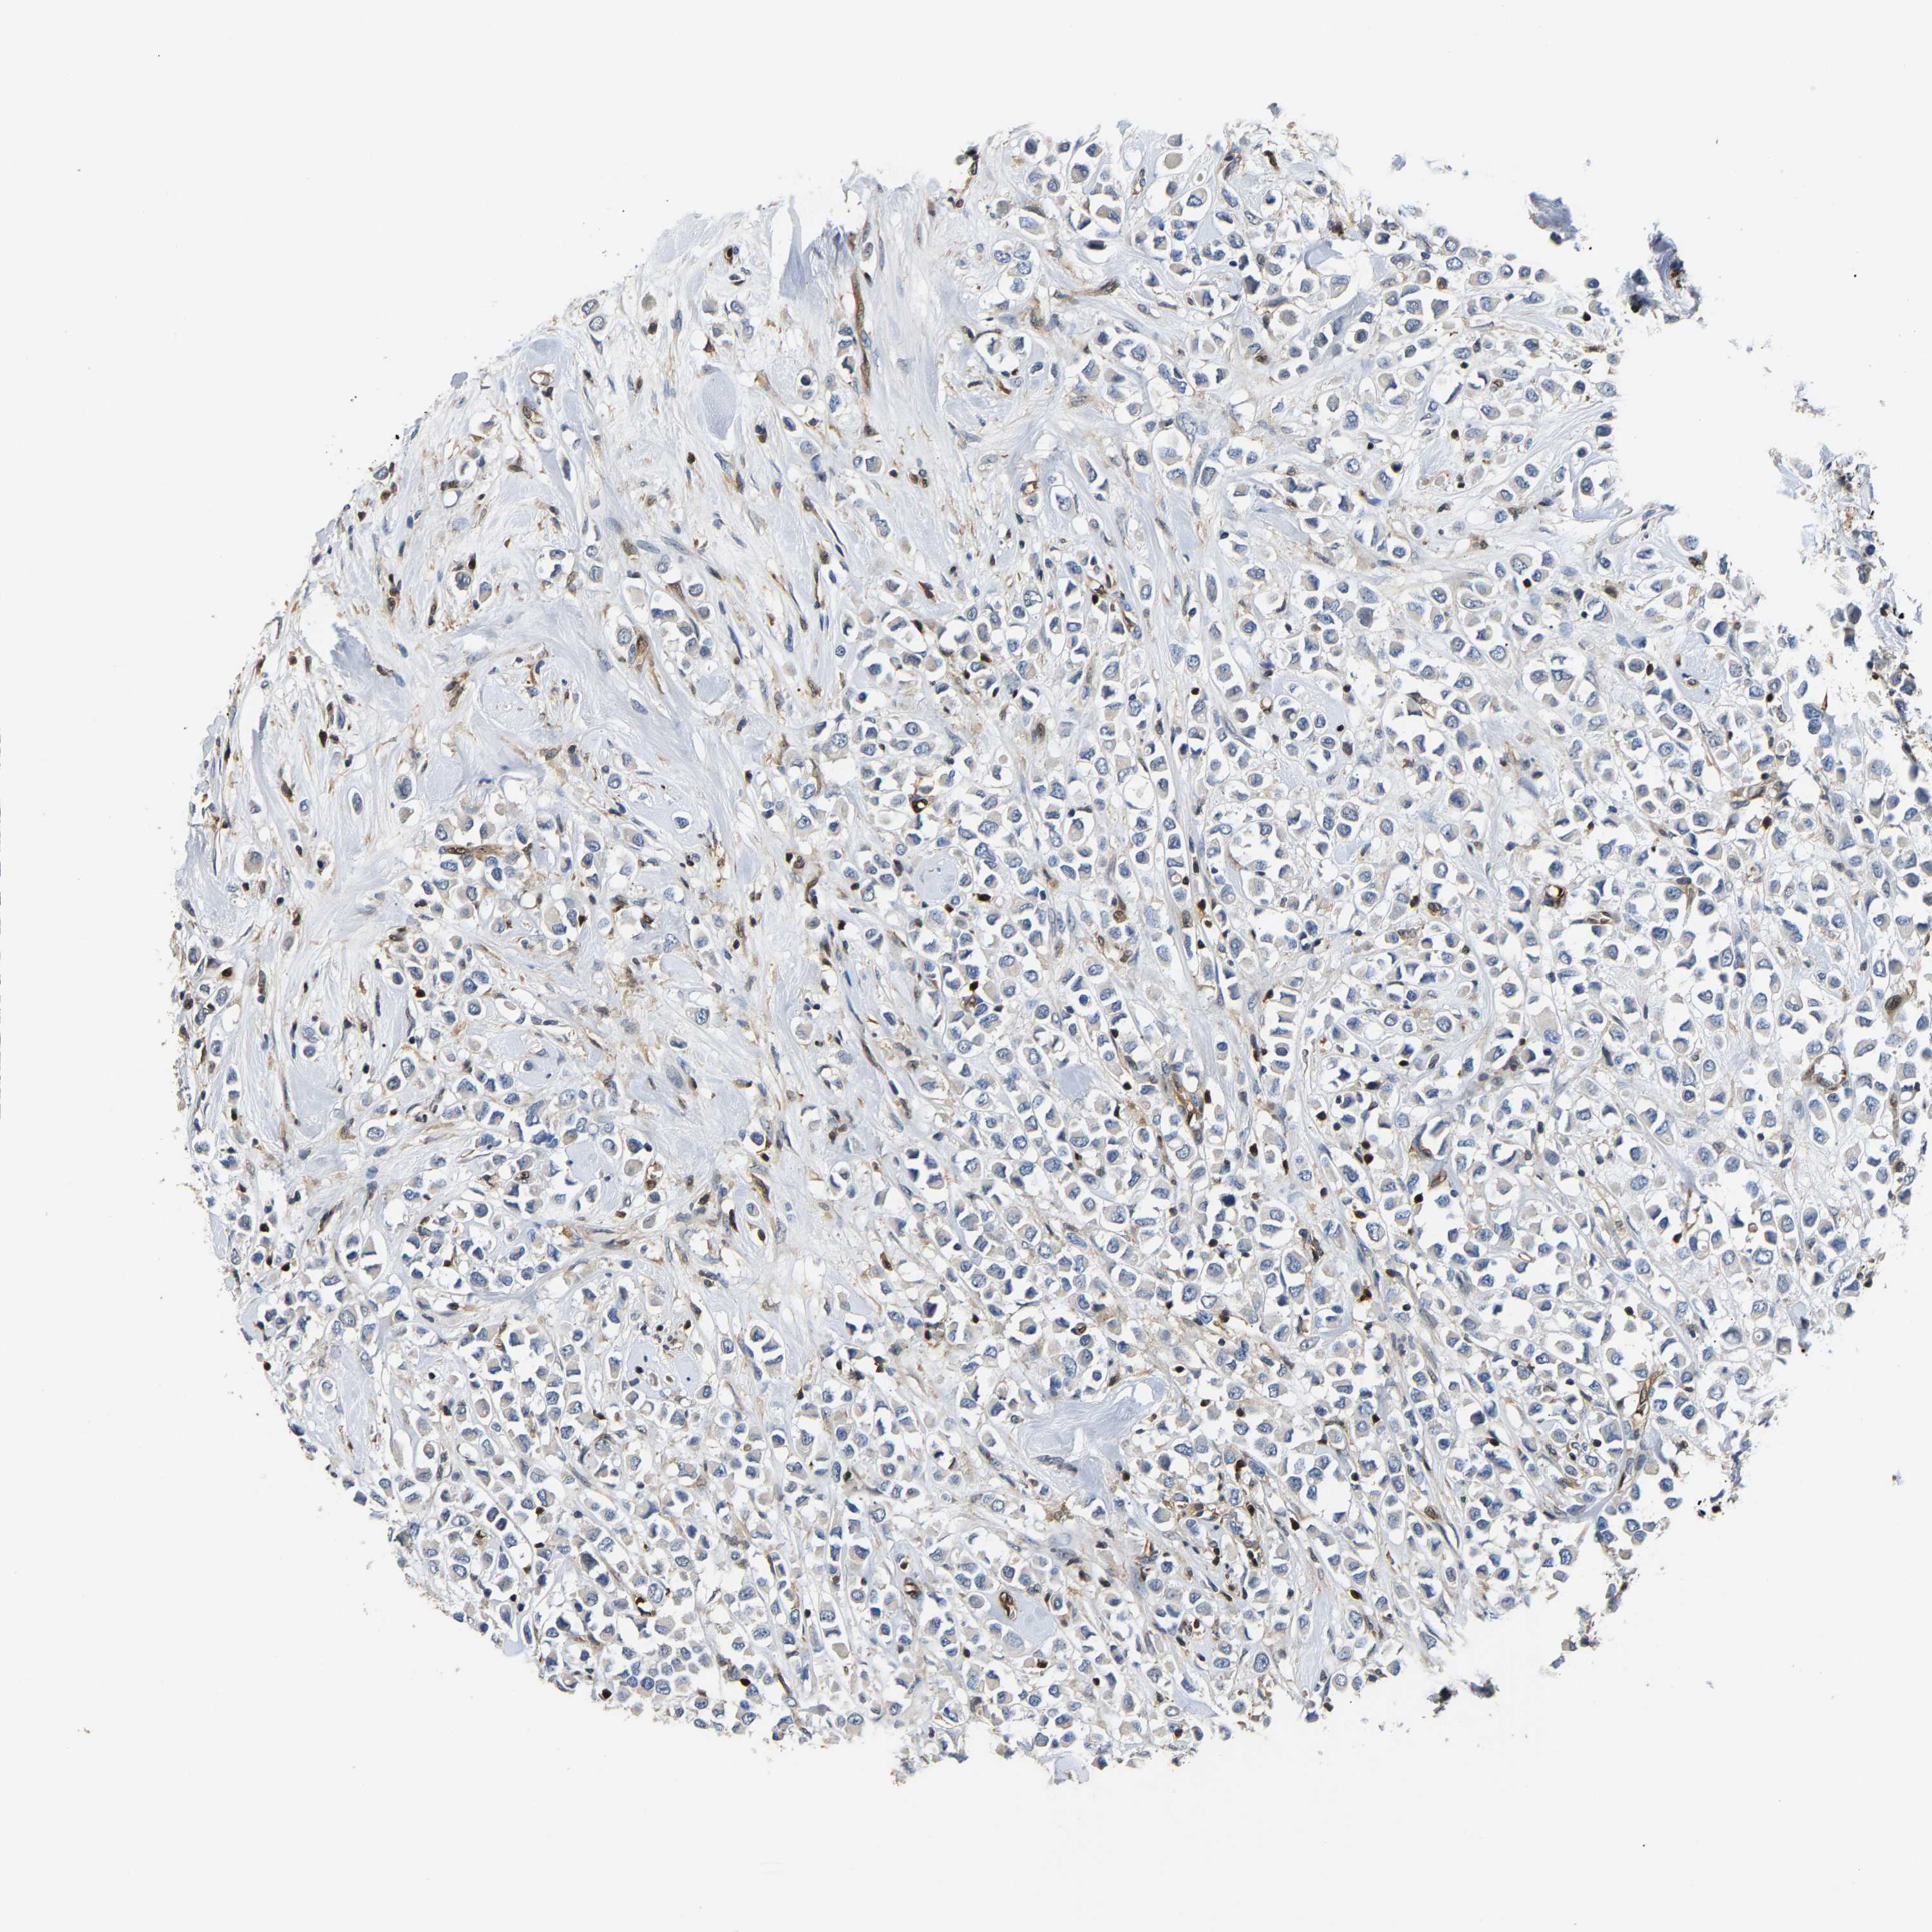

CANCER BREAST CANCER Show tissue menu

BRCA TCGA BRCA VALIDATION PROTEIN EXPRESSION